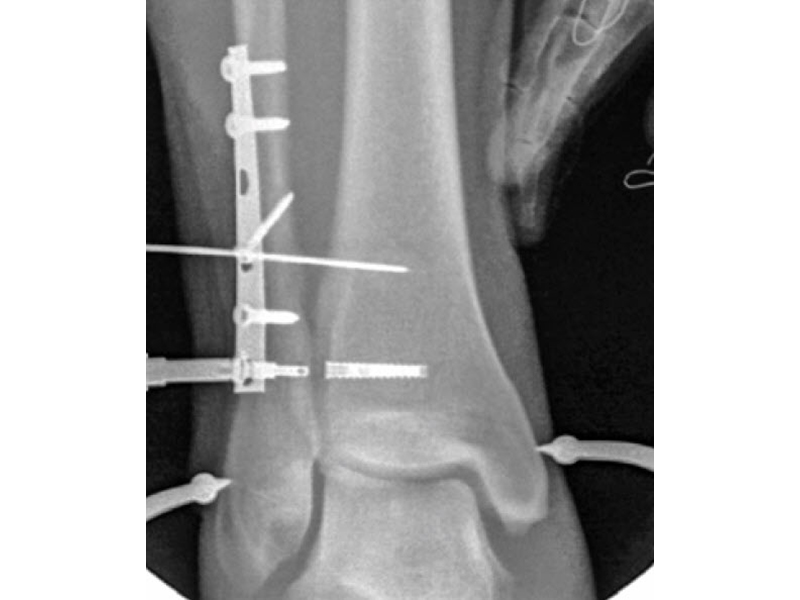

A 34-year-old woman was injured while riding a motor scooter sustaining an ankle fracture with associated syndesmotic injury (Fig 6a). The fibula was reduced anatomically and stabilized with a 1/3 tubular plate (Fig 6b). The unstable syndesmosis was reduced and provisionally stabilized with a K-wire and clamp (Fig 7) before FIBULINK Implant System implantation (Fig 8). The patient had an uneventful recovery (Fig 9).